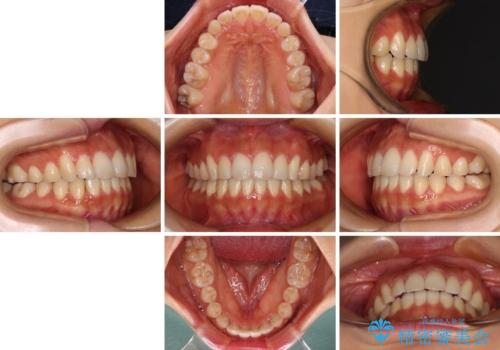

カリエールディスタライザーを併用した、咬み合わせ改善のインビザライン矯正

- 飛び出した前歯と口元の突出感を気にして来院された患者様です。

奥歯の咬み合わせを見ると、上顎が下顎に対して相対的に前方にありました。

口元の突出感を改善するためには、上顎臼歯を後方に移動させた咬み合わせにする必要があります。

インビザライン単体で改善することも可能ですが、達成する可能性が高くないため、カリエールディスタライザーという補助装置を併用して、より確実性を上げることとしました。

奥歯の咬み合わせを改善しながら、並行してインビザラインで歯列を整えることとしました。

カリエールディスタライザーを併用したことで、確実かつ短期間で治療を終えることができました。